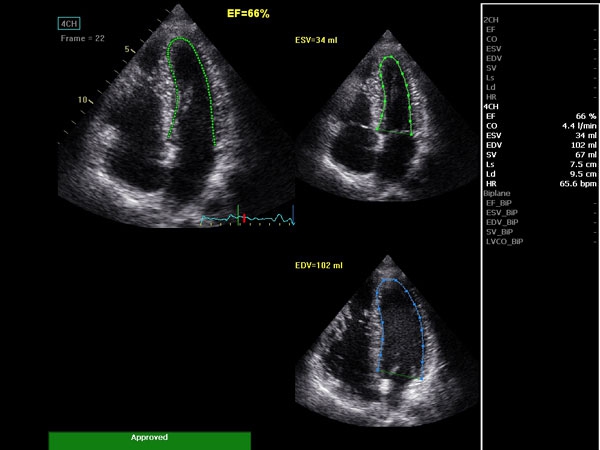

Ключевым сегментом диагностической медицины, где функционал данного устройства раскроется в полной мере, является кардиология. Благодаря высокочастотным датчикам и превосходным изображениям, можно рассмотреть без лишнего шума детали сердца пациента и поставить точный эффективный диагноз.

• AutoEF (Auto Ejection Fraction) — функция автоматической недоплеровской количественной оценки глобальной сократительной функции левого желудочка с выделением зоны интереса по технологии спекл-трекинга.

• AFI (Automated Function Imaging) — автоматическое отображение функции ЛЖ — функция позволяет производить качественную и количественную недоплеровскую оценку региональной сократительной функции левого желудочка.

AUTO 2D EF:

Да